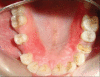

The use of rigid connectors in 5-unit fixed dental prosthesis with a pier abutment can result in failure of weaker retainer in the long run as the pier abutment acts as a fulcrum. Non-rigid connector placed on the distal aspect of pier seems to reduce potentially excess stress concentration on the pier abutment.